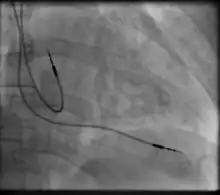

Permanent transvenous pacing

Permanent pacing with an implantable pacemaker involves transvenous placement of one or more pacing electrodes within a chamber, or chambers, of the heart, while the pacemaker is implanted under the skin below the clavicle. The procedure is performed by incision of a suitable vein into which the electrode lead is inserted and passed along the vein, through the valve of the heart, until positioned in the chamber. The procedure is facilitated by fluoroscopy which enables the physician to view the passage of the electrode lead. After satisfactory lodgement of the electrode is confirmed, the opposite end of the electrode lead is connected to the pacemaker generator.

CRT devices have at least two leads, one passing through the vena cava and the right atrium into the right ventricle to stimulate the septum, and another passing through the vena cava and the right atrium and inserted through the coronary sinus to pace the epicardial wall of the left ventricle. Often, for patients in normal sinus rhythm, there is also a lead in the right atrium to facilitate synchrony with the atrial contraction. Thus, the timing between the atrial and ventricular contractions, as well as between the septal and lateral walls of the left ventricle can be adjusted to achieve optimal cardiac function.